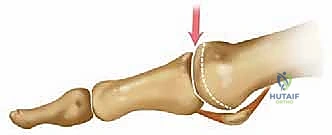

هل تعاني من ألم مستمر وتيبس مزعج في مفصل إبهام قدمك الكبير؟ هل أصبحت الأنشطة اليومية البسيطة مثل المشي، صعود الدرج، أو حتى ارتداء الأحذية العادية تحديًا مؤلمًا يسرق منك متعة الحياة؟ إذا كانت إجابتك نعم، فأنت لست وحدك في هذه المعاناة. يُعرف هذا التيبس والألم طبياً باسم "تيبس إبهام القدم" أو "الفصال العظمي في مفصل إبهام القدم الكبير" (Hallux Rigidus). إنها حالة شائعة ومؤلمة للغاية تؤثر على الملايين حول العالم، وتعتبر من أكثر أسباب آلام القدم التي تدفع المرضى لزيارة عيادات العظام.

يمكن أن تتطور هذه الحالة تدريجيًا وبصمت، بدءًا من ألم خفيف متقطع بعد مجهود طويل، ثم تزداد حدة لتصبح ألماً مستمراً يحد من حركتك بشكل كبير، ويؤثر على طريقة مشيك، مما قد يؤدي لاحقاً إلى آلام في الركبة والورك وأسفل الظهر نتيجة لاختلال توازن الجسم أثناء المشي لتجنب الألم.

مع تقدم المرض واستمرار الاحتكاك العظمي، يمتد تآكل الغضروف هذا إلى المركز، وفي النهاية يشمل الجانب الأخمصي (السفلي) لرأس المشط. بالتزامن مع تآكل الغضروف، واستجابة للاحتكاك والضغط غير الطبيعي، يبدأ الجسم في محاولة إصلاح نفسه بشكل خاطئ، مما يؤدي إلى تكوّن نتوءات عظمية حادة (Osteophytes) حول حواف المفصل.

هذه النتوءات العظمية تعمل كمصدات ميكانيكية تمنع الإبهام من الانثناء لأعلى (Dorsiflexion) أثناء المشي، مما يسبب ألماً حاداً وتقلصاً شديداً في نطاق حركة المفصل. هذا التطور تدريجي ولكنه لا هوادة فيه، وقد ينتهي بتيبس كامل للمفصل.

- تورم والتهاب: حول المفصل، خاصة في الجزء العلوي منه.

- تكوّن نتوء عظمي (Bunion أو Bone Spur): ظهور كتلة صلبة على الجزء العلوي من المفصل، تسبب ألماً عند احتكاكها بالحذاء.